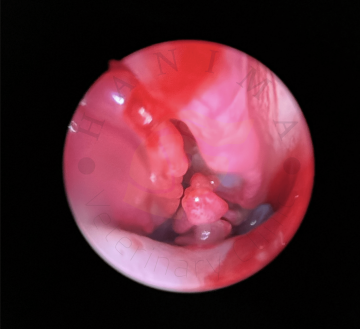

bronchoalveolární laváž (BAL), klinické a RTG vyšetření hrudníku (srdce a plíce), diagnostika a terapie zánětlivých nemocí plic (bronchitídy, pneumónie), psincový kašel, měření krevního tlaku, endoskopické vyšetření horních cest dýchacích rigidním endoskopem,...